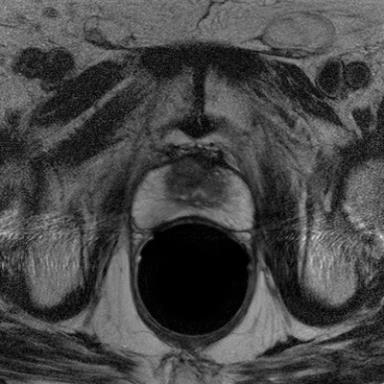

Modern deep neural networks struggle to transfer knowledge and generalize across diverse domains when deployed to real-world applications. Currently, domain generalization (DG) is introduced to learn a universal representation from multiple domains to improve the network generalization ability on unseen domains. However, previous DG methods only focus on the data-level consistency scheme without considering the synergistic regularization among different consistency schemes. In this paper, we present a novel Hierarchical Consistency framework for Domain Generalization (HCDG) by integrating Extrinsic Consistency and Intrinsic Consistency synergistically. Particularly, for the Extrinsic Consistency, we leverage the knowledge across multiple source domains to enforce data-level consistency. To better enhance such consistency, we design a novel Amplitude Gaussian-mixing strategy into Fourier-based data augmentation called DomainUp. For the Intrinsic Consistency, we perform task-level consistency for the same instance under the dual-task scenario. We evaluate the proposed HCDG framework on two medical image segmentation tasks, i.e., optic cup/disc segmentation on fundus images and prostate MRI segmentation. Extensive experimental results manifest the effectiveness and versatility of our HCDG framework.